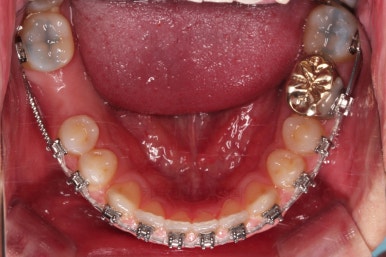

초진 시의 입안 모습입니다.

어금니가 빠져서 결손치아가 있고 치아 사이에 틈새도 있어서 교정치료도 함께 원한다고 내원해 주셨어요.

사진에서 보시는 바와 같이 윗니 1개, 아랫니 1개의 결손 부위가 보입니다.

윗니 어금니 중에는 신경치료를 마무리 못하고 임시재료로 메꿔뒀던 부위도 보이고요.

교정장치를 부착하고 충치치료는 별개로 진행되었어요.

이번에 선택하신 장치는 자가결찰(철사를 잡아주는 뚜껑이 자체적으로 달려있는) 메탈(금속)장치이며 엠파워 메탈이라고 하는 장치입니다.

세라믹에 비해 많이 보인다는 단점이 있지만 저렴하고 튼튼한 관리가 약간은 더 편하다는 장점이 있어요.

틈새는 서서히 조여서 없애주고요.

충치치료가 완료된 부위는 골드 크라운(금니)이 씌워졌어요.

임플란트를 하기에 적절한 사이즈로 공간은 맞춰줍니다.